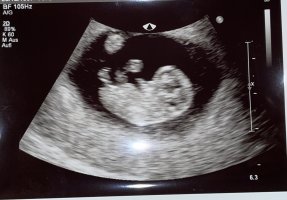

Ramzi teorisine göre bebeğimin cinsiyeti nedir bakar mısınız ?

Kız gibi gördüm hayatım. Resim tarafımdan düzenlendi bilgin olsun. Rabbim hayırlısını versin. Kese yapısı kız gibi duruyor. Tabiki Gaybı bilen sadece Allah'tır. Biz görebildiğimiz kadarını söyleriz sevgiler sunuyorum.

Hayatım sen bana görüntü atmışsın ben sadece kese durumuna göre değerlendirdim. Daha ilerleyen zamanlarda ( ki resimde kesen görünüyordu hayatım ) başka şekilde resim edinir isen tabiki yeniden değerlendirmek isterim.